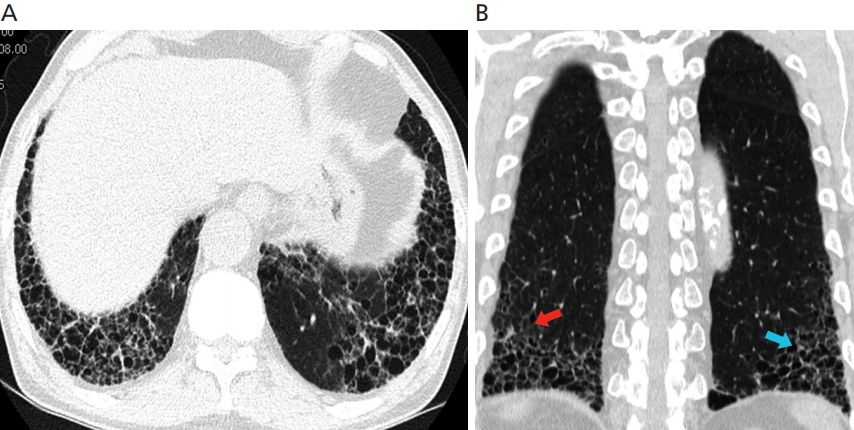

- 진단: 흉부 CT, 폐 기능 검사, 조직 생검 등을 활용

- 고해상도 흉부 CT와 폐조직 검사, 다양한 감별진단(자가면역질환, 약물, 환경성 노출 가능성 배제) 과정이 필요합니다.

- 섬유화가 진행되며 폐의 탄력성이 떨어지고, 산소 교환 능력이 감소합니다.

- 이로 인해 점차 호흡곤란, 마른기침 등 증상이 발생하며, 폐 기능이 꾸준히 저하됩니다.